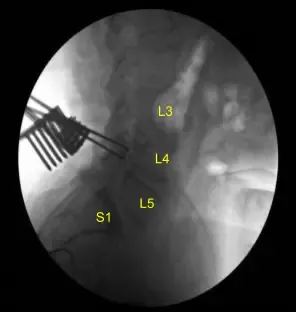

The C-arm unit, which was draped sterilely, was brought into the field and used to confirm the level. Neuronavigation array was affixed to the right superior posterior iliac crest with two Schanz pins after infiltrating with local anesthesia and making #15 blade stab incisions.

The patient was sterilely draped. CT scan was obtained. Data was transferred to the neuronavigation computer. Accuracy was verified. Neuronavigation techniques were used to morselized bone for arthrodesis autograft. Leksell rongeurs, Kerrison rongeurs and electric high-speed drill under continuous sterile irrigation were used to perform complete L4-5 laminectomy and facetectomies, completely neurolyzing with Penfield-Metzenbaum technique the L4, L5 and S1 nerve roots.

Epidural bleeding was controlled with Surgiflo hemostatic matrix and bipolar electrocautery. Bone bleeding was controlled with bone wax. L4-5 and L5-S1 interbody arthrodesis was performed by retracting the thecal sac with a nerve root retractor, performing annulotomy with a bayoneted #15 blade scalpel.